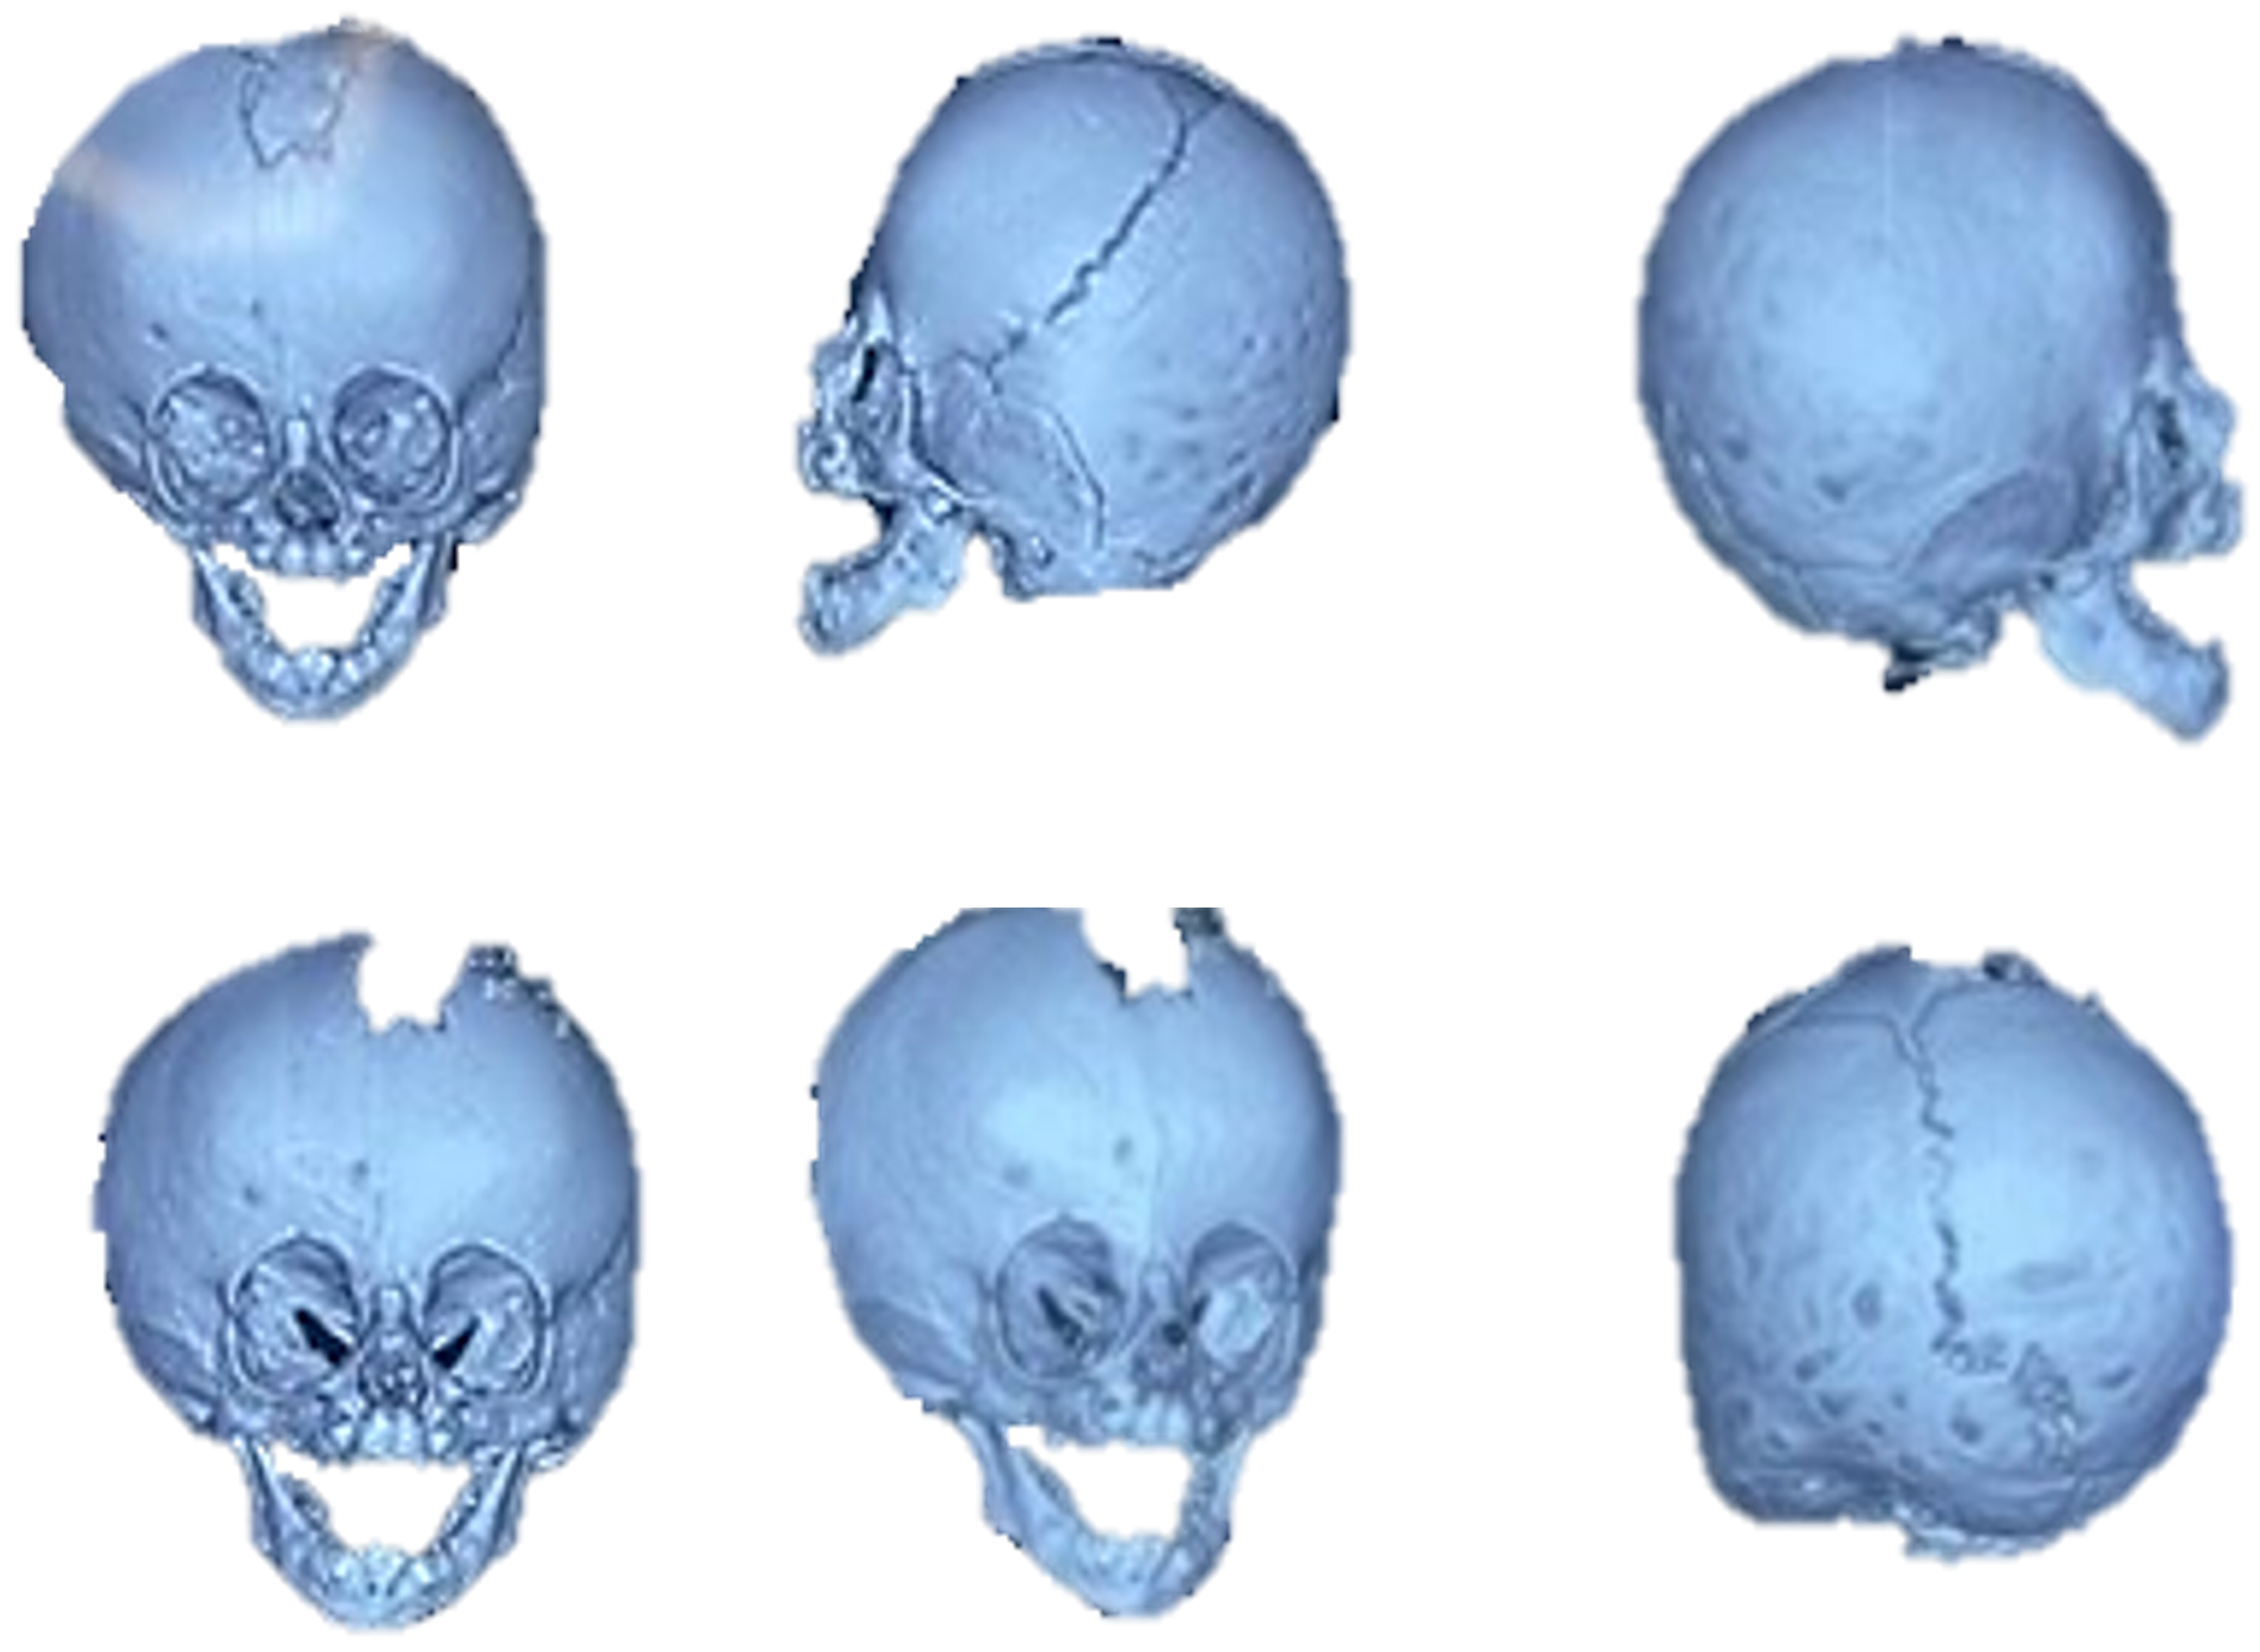

3.7. Case 7: Metopic Craniosynostosis and Trigonocephaly

A 9-month-old female patient presented with metopic craniosynostosis and trigonocephaly, characterised by premature fusion of the metopic suture, resulting in a triangular frontal deformity and possible hypertelorism. The recommended treatment in this situation is cranial remodelling surgery. Figure 43 shows different aspects of defect identification using tomographic images.

The medical team decided to perform the surgery assisted by 3D printing technology using customised cutting guides.

To facilitate surgical planning and simulation, a test model of the deformed skull of the child was used in addition to the necessary cutting guide for developing the intervention. Figure 44 shows the skull’s anatomical test model and the cutting guide’s test model, both printed in PLA. And Figure 45 shows the digital models of the two medical devices.

Figure 43. Different aspects of deformity identification (tomographic image).

Figure 44. Anatomical test model of the skull (left). Test model of the cutting guide and planning of cuts on the cranial bone (right).

Figure 45. Digital models of the skull and the cutting guide.